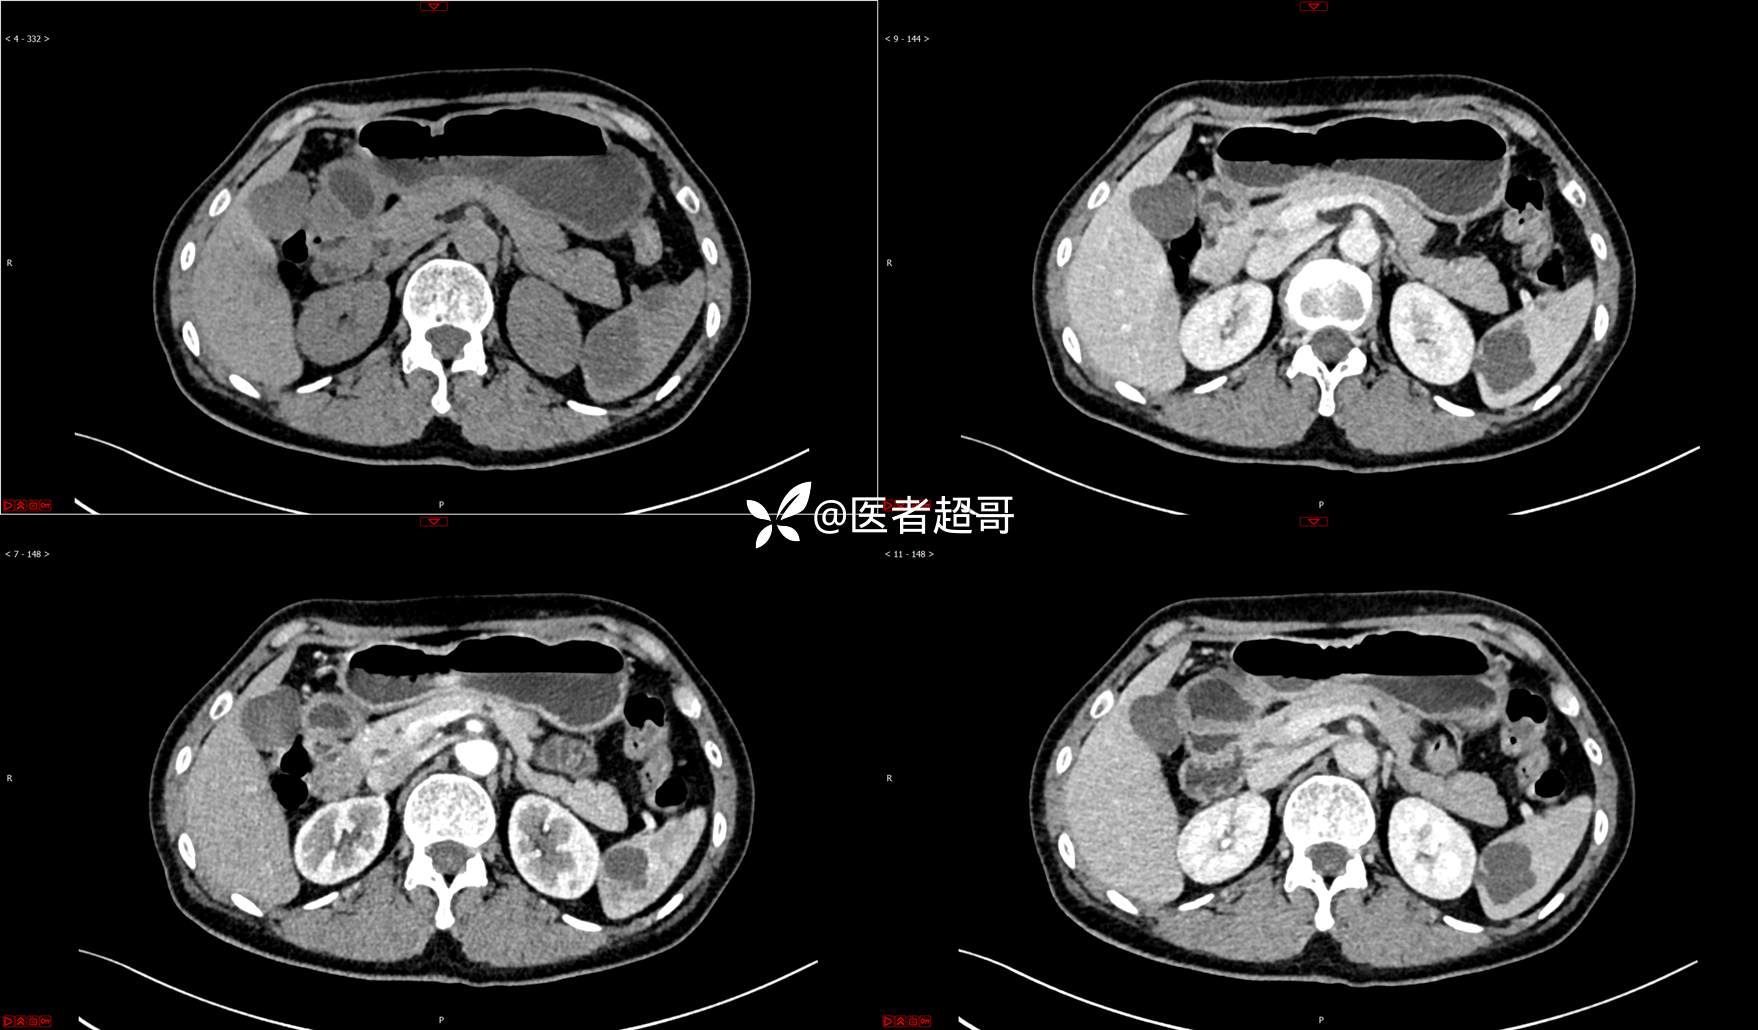

【影诊笔记739】脾脏囊性占位,查体偶发,请赏析,有病理!

女,6岁 0201215 02

主 诉:查体发现脾脏囊性占位4年。

现病史:患者4年前于人民医院查体时发现脾脏囊性占位。-04-20到我院复查,行上腹平扫+强化CT示:肝囊肿,脾脏囊实性占位,囊腺瘤?当时无明显症状,未行任何治疗。4个月前无明显原因及诱因开始偶尔出现左上腹疼痛,为隐痛,伴腰部放射痛,无腹胀、腹泻,无恶心、呕吐,无发热、畏寒、全身乏力,无胸痛、胸闷等其它不适。在外未行特殊治疗,今为求进一步诊治来我院就诊,行腹部彩超(肝、胆、胰、脾、肾)示:脾脏房囊性肿物。门诊以“脾占位性病变”收入院。发病以来,患者神志清楚,精神可,饮食可,睡眠欠佳,大小便正常,近期体重无明显变化。